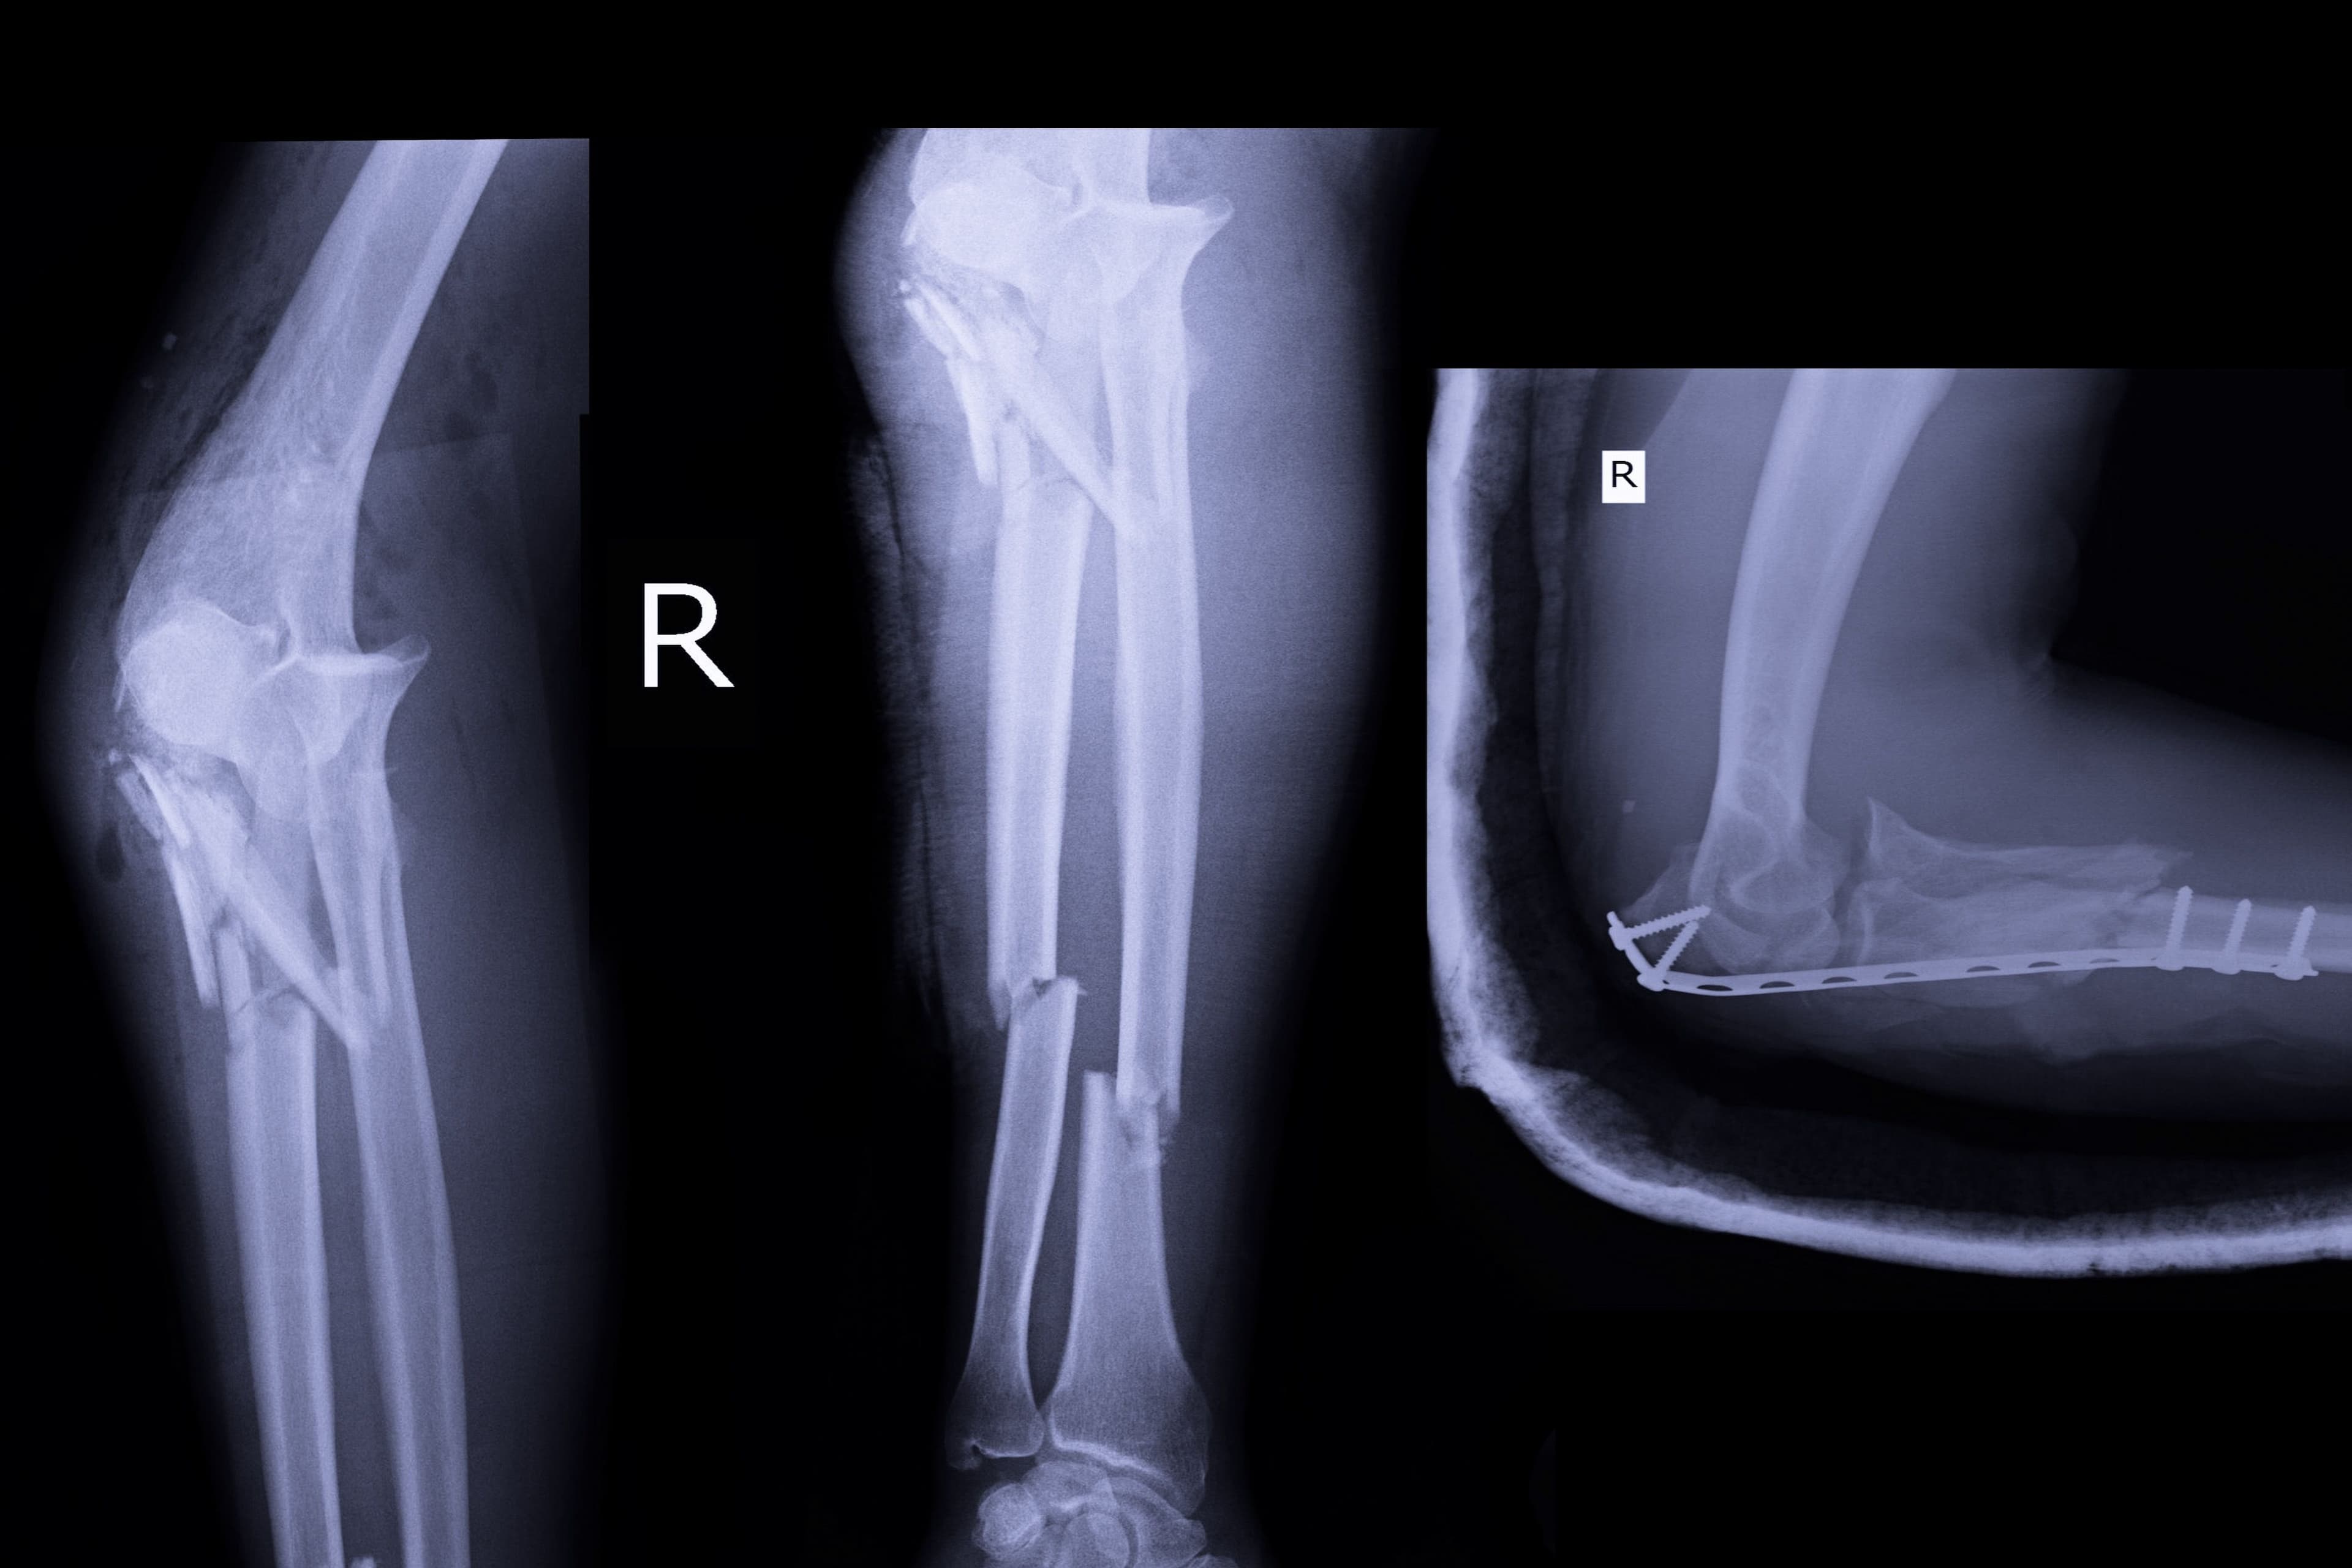

- Surgery: In the case of a complex fracture, surgery may be necessary to achieve optimal healing. There are several options available to the surgeon: open reduction and internal fixation, which involves putting the bone fragments back into place and fixing them with metal hardware; external fixation, which uses pins or screws inserted into the bone for external stabilisation; intramedullary nailing, which reinforces the bone from the inside with a metal rod; and finally, bone grafting, used to replace the missing bone with natural or synthetic bone tissue. The choice of technique depends on many factors, such as the type of fracture, the patient's age and physical condition.